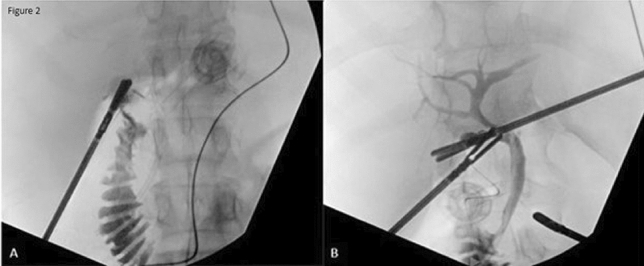

Methods: We present a 72-year-old male with prior radical cystectomy and neobladder creation complicated at the time by neobladder-cutaneous fistula and wound infection requiring revisional surgery and incisional hernia repair with mesh. He developed a large recurrent incisional hernia and underwent open hernia repair with bilateral anterior component separation, extensive lysis of adhesions, removal of prior mesh, and placement of a biologic mesh (Strattice™ RTM) in an underlay and onlay fashion. Intraoperatively, the defect measured 20 cm long by 14 cm wide. Postoperatively, he was treated for neobladder infection and CT cystogram found no extravasation from the neobladder. He presented to the emergency department 6 weeks after surgery with spontaneous partial midline wound dehiscence, with exposure of the onlay mesh and drainage of clear fluid, which was confirmed to be urine by fluid creatinine level. Repeat CT scan demonstrated a filling defect at the anterior wall of the neobladder with contrast leaking into a contained collection interposed between the anterior abdominal wall and the underlay mesh, extending superiorly between the small bowel loops and dehiscence of the midline abdominal wound. The patient was treated with a course of antibiotics and indwelling Foley catheter and bilateral nephrostomy tubes for urine diversion.

Results: Three months later, repeat CT cystogram demonstrated resolution of the leak and the nephrostomy tubes and Foley catheter were removed. The patient has continued daily wound care with significant reduction in size of the midline wound and increasing granulation tissue around the onlay mesh. He has not required further admissions to hospital and there has been no hernia recurrence so far.